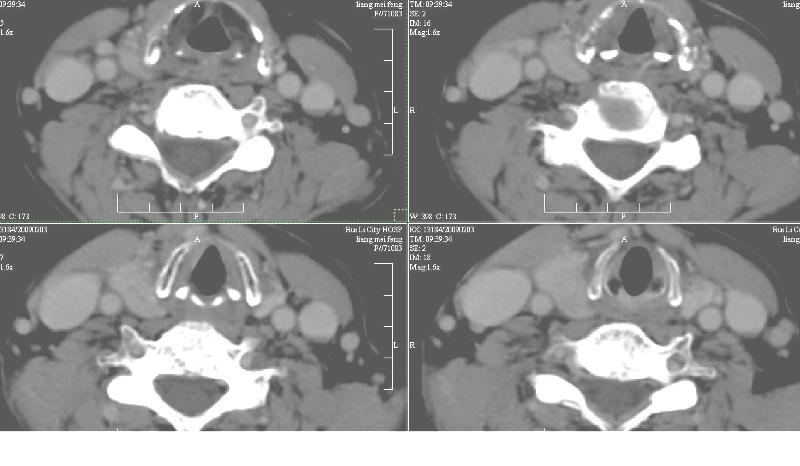

双侧甲状腺稍肿,右侧触及包块,随吞咽上下活动。 1、双侧甲状腺肿(摄碘率降低)。2、右侧甲状腺多发腺瘤,必要时增强。平扫

增强:1、双侧甲状腺肿。2、平扫甲状腺内多发占位病变,增强显示不清楚,境界欠清,请结合临床考虑甲状腺瘤。